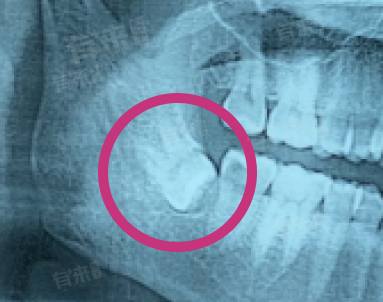

横生智齿不会自然停止生长,其生长受多种因素影响,即便生长速度缓慢,也会持续对周围组织产生影响,难以自行终止生长进程,还可能引发一系列口腔问题。横生智齿是指智齿以水平方向生长,由于人类颌骨在进化过程中逐渐变小,留给智齿萌出的空间不足,使得智齿无法正常直立生长。

- 在生长过程中,横生智齿的牙冠会持续挤压邻牙、牙槽骨以及牙龈组织。从解剖结构来看,牙齿的生长动力源于牙周膜中的成纤维细胞和破骨细胞的协同作用,只要牙齿未完全萌出,牙周膜就会持续发挥作用,促使牙齿生长。所以,横生智齿会不断寻找生长空间,向周围施加压力,这一过程不会自行停止。